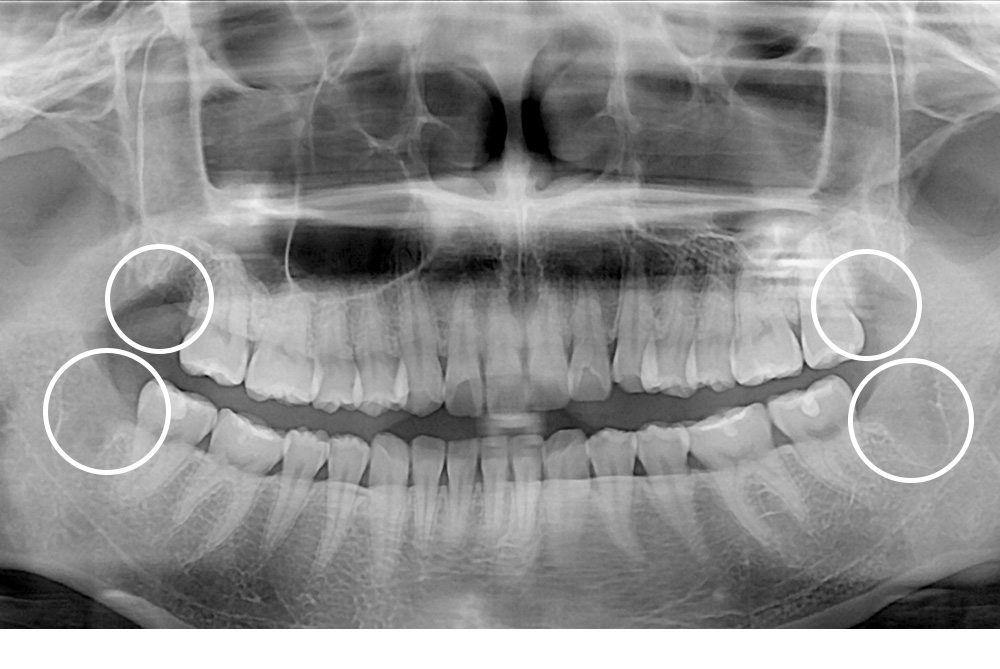

치료후 : 2019-03-09

세종치과는 구강악안면외과학 박사이신 원장님이 발치하는 치과입니다.